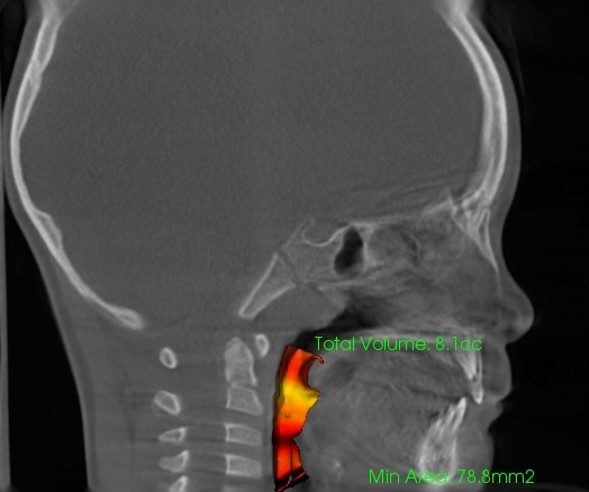

気道容積

鼻腔容積

- 診断根拠:CT等による鼻腔・気道・骨格等の画像及び数値解析

- 評価指標:気道容積・鼻腔容積の数値変化、骨格変化の数値解析、舌骨の位置や姿勢の改善評価等

※気道容積・鼻副鼻腔容積の変化イメージ